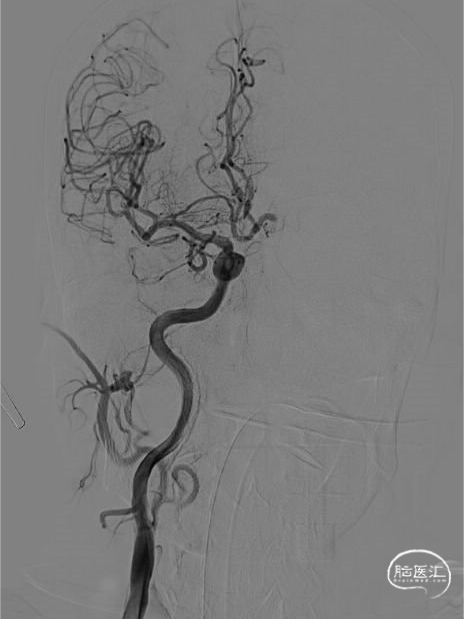

在长鞘支撑下将React™ 71一次性颅内血栓抽吸导管上高至血栓近端,React™ 71一次性颅内血栓抽吸导管到位后行持续负压抽吸。尽管患者血管迂曲,但React™ 71一次性颅内血栓抽吸导管轻松到位。

抽吸后造影提示:闭塞血管成功三级再通。